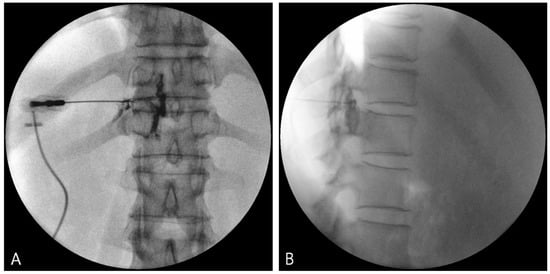

Patients were placed in a prone position on a fluoroscopic-compatible table. The needle entry site was prepared and draped in a sterile fashion. A fluoroscope was placed obliquely toward the ipsilateral side. After local infiltration, a 22-G Quincke needle was introduced inferior to the pars interarticularis under fluoroscopic guidance at the level of pathology.

The needle tip position was adjusted to inferior to the pedicle in the anteroposterior view. To minimize the possibility of vascular injury, the needle tip was positioned in the lower posterior portion of the intervertebral foramen in the lateral view of the fluoroscopic image (Figure 1).

Figure 1.

Fluoroscopic images of TFEI. (A) Anteroposterior (AP) view. (B) Lateral view. TFEI: Transforaminal epidural injection.